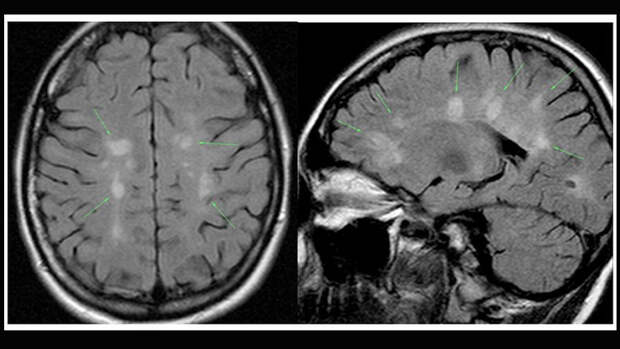

Рассеянный склероз поражает нервную систему, головной и спинной мозг. При этом аутоиммунном заболевании иммунная система начинает бороться с оболочкой нервных волокон - миелином. Из-за этого функция нервов ухудшается, и начинаются проблемы со связью между мозгом и телом.